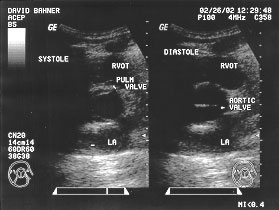

Cardiac cycle - aortic view